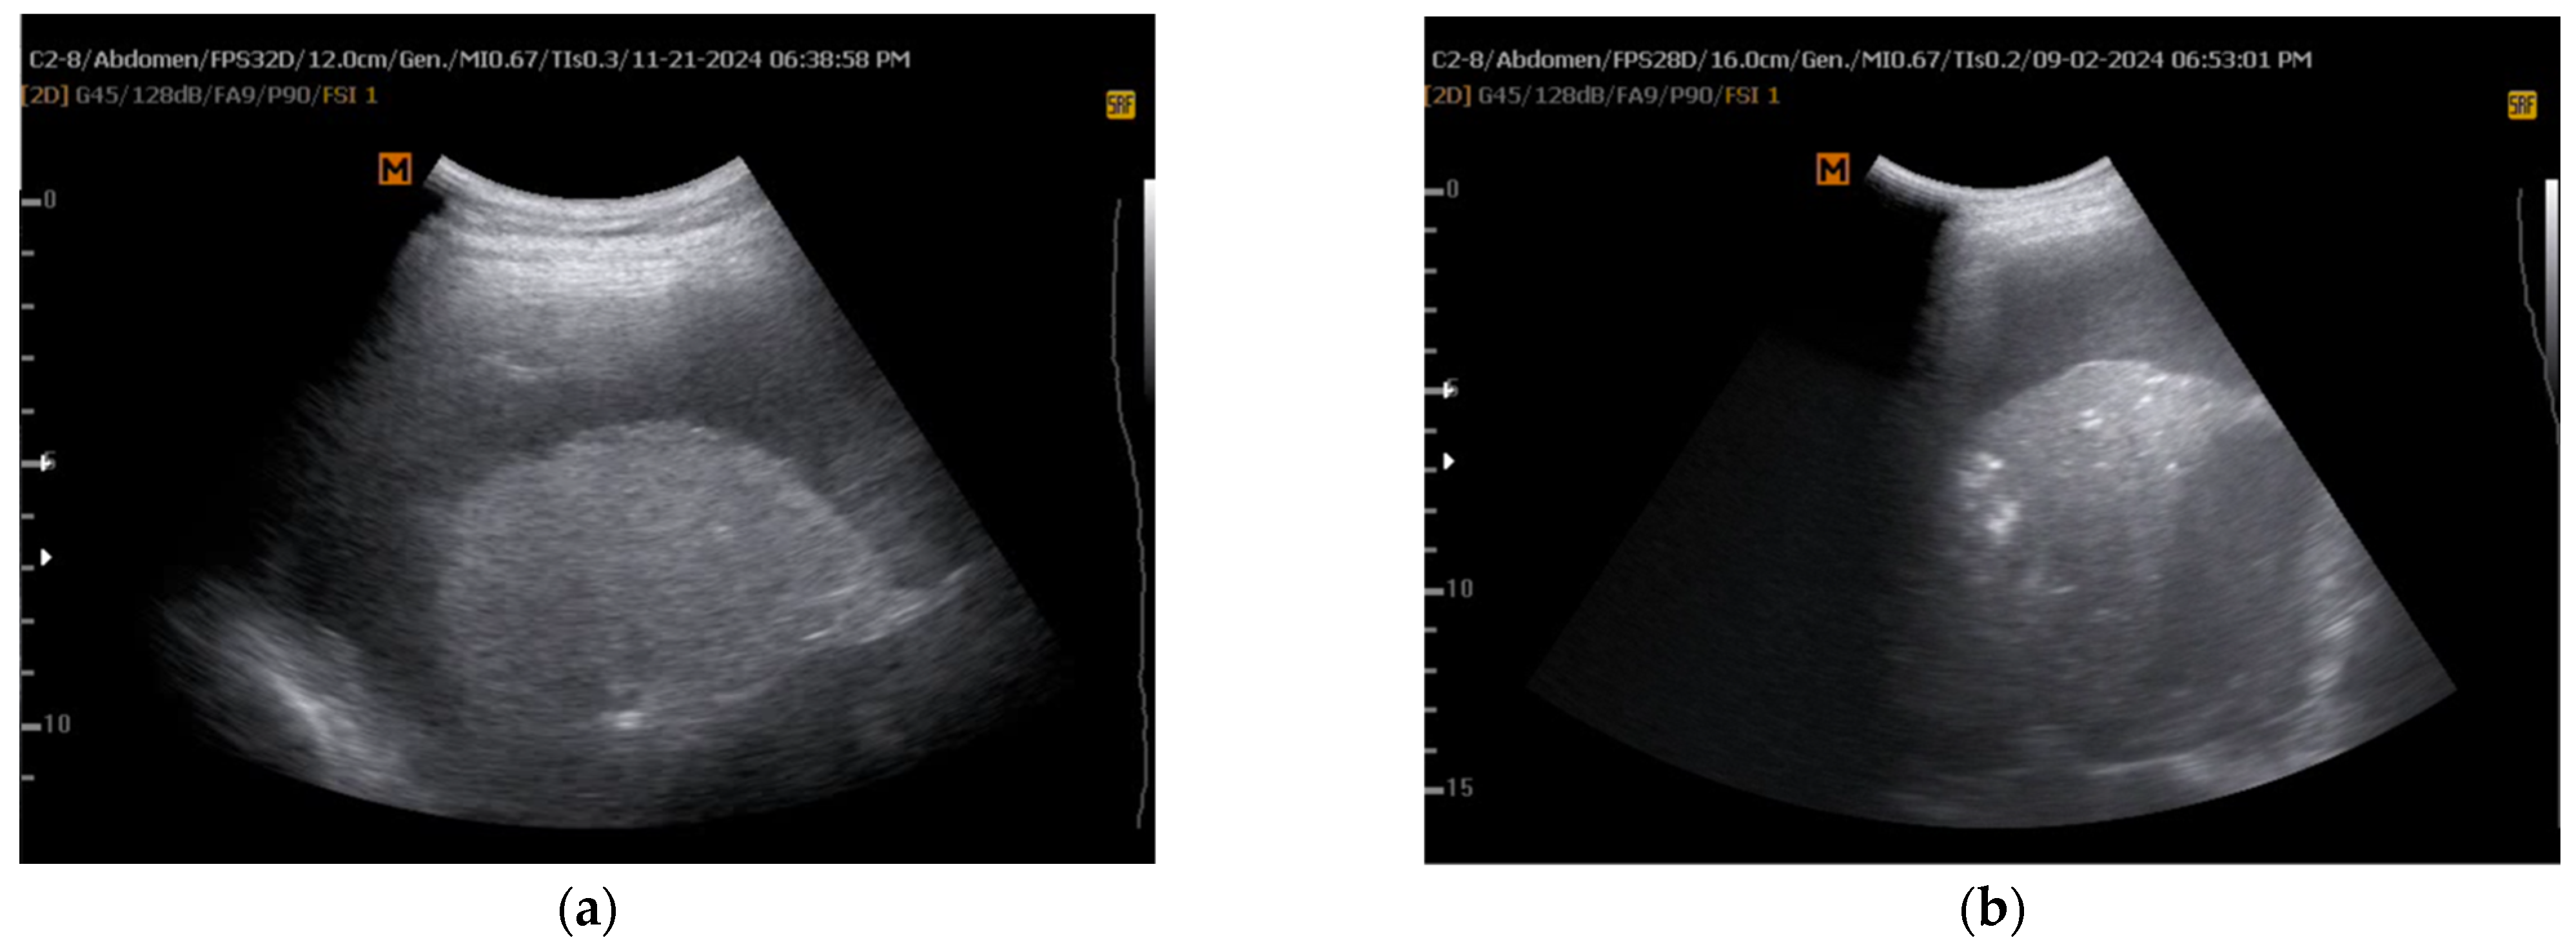

| Hassan et al. [21] | 2021 | Validate TUS predictors of NEL | Prospective cohort | 29 patients with pleural effusion | M-mode, lung/liver echogenicity (LLE) ratio | M-mode alone was a poor predictor (AUC = 0.48), LLE ratio was better (AUC = 0.77) | LLE may serve as a better predictor for NEL than M-mode alone | Small sample size, single-center study |

| lung/liver echogenicity (LLE) ratio | Compares grayscale pixel density of lung and liver via ImageJ software | Predicting lung re-expansion after pleural drainage | LLE > 1.6 predicts NEL with AUC = 0.77 | Simple, reproducible, quantitative | Limited validation, small study population, dependent on image quality | Lacks direct validation against; potential role as adjunct to manometry | Requires software (ImageJ) and proper grayscale calibration, moderately operator-dependent | Larger, multicenter studies, AI-based echogenicity analysis, validation in different effusion types |